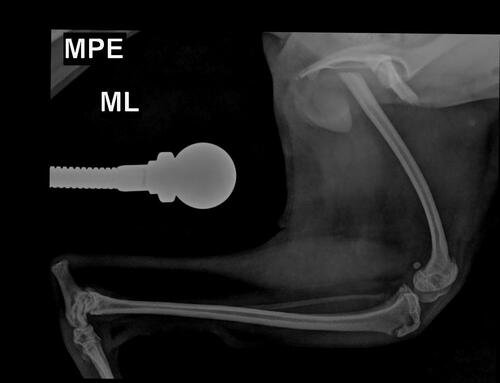

minha cachorrinha Mandy é uma shitzu de 7 meses e ela além de ser mto sapeca e agitada, ela já tinha quebrado o braço um mês atrás 🥲 não deu duas semanas ela fraturou o fêmur brincando com nosso outro cachorro Billy

vou colocar aqui em anexo todo o laudo dela